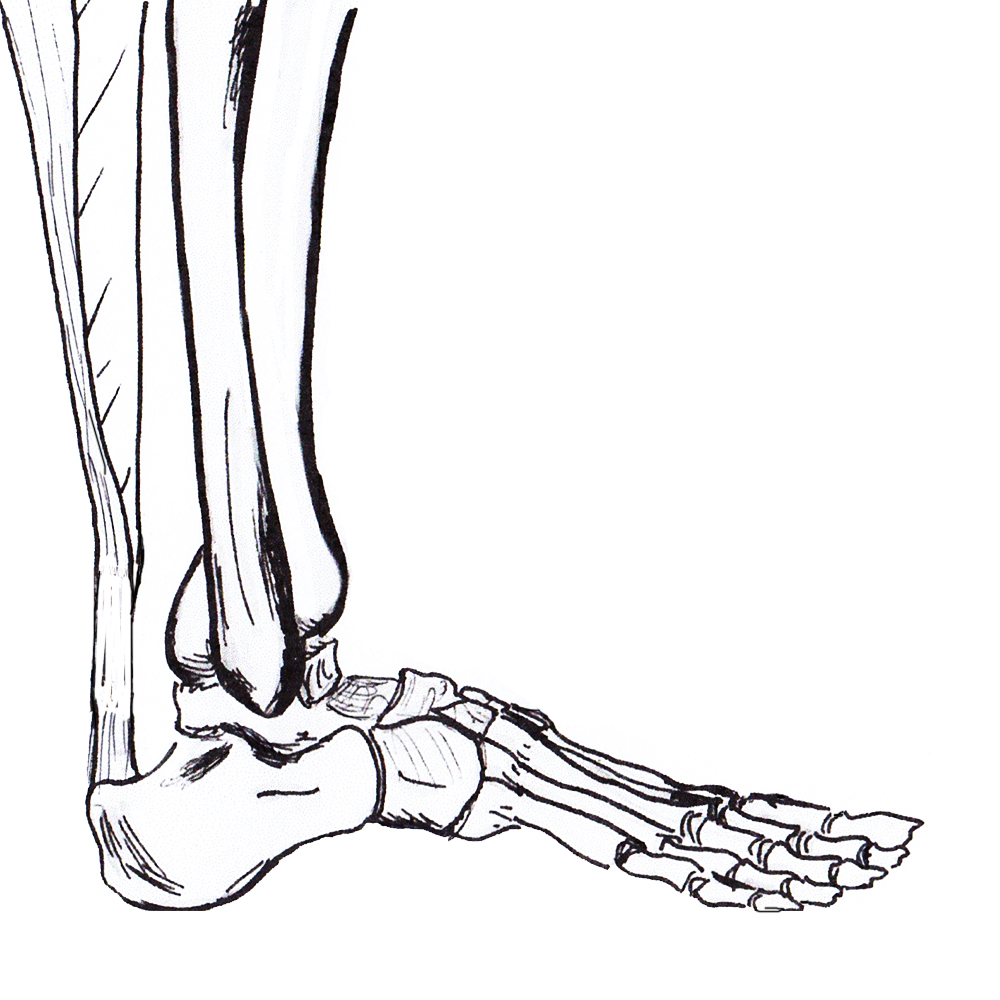

Anatomy

Gastrocneumic and soleus tendon

- longest tendon in human body

- fibres spiral 90° before inserting on superior calcaneal tuberosity

- medial gastrocs inserting posteriorly

- allows elastic recoil & energy storage

Paratenon

- allows smooth tendon movement

Blood supply

- paratenon

- small amount muscle proximally and calcaneum distally

- watershed area 2 - 6 cm proximal to calcaneal tuberosity / area of rupture

Plantaris

- present in 90% population

- medial to Tendo-achilles